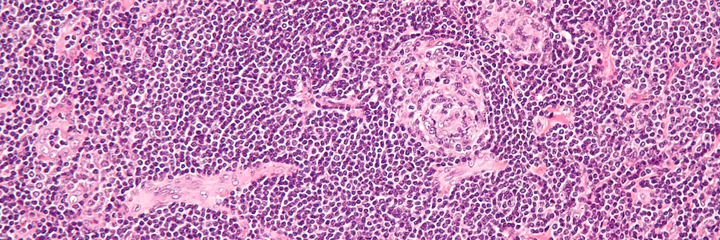

Castleman disease (CD) describes a group of rare lymphoproliferative disorders that involve enlarged lymph nodes, and a broad range of inflammatory symptoms and laboratory abnormalities. Whether Castleman disease should be considered an autoimmune disease, cancer, or infectious disease is currently unknown.1